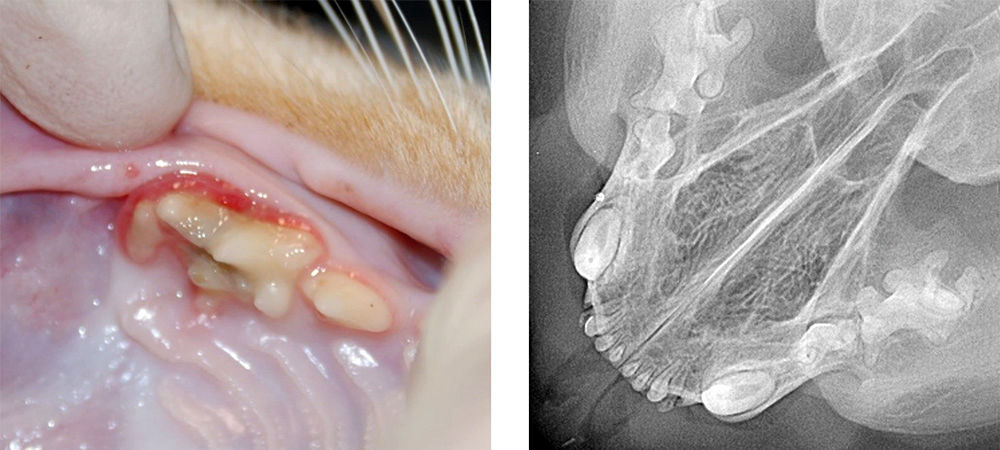

The complete removal of dental fragments during or after tooth extraction in horses is often the aim in clinical practice but is not strictly necessary in all cases. The aim of this article is to formulate an evidence-based and practice-oriented basis for decision-making regarding the indication for or against the removal of dental fragments, based on current literature and personal experience. Retained tooth fragments, particularly apical root remnants, represent a significant risk factor for postoperative complications. Gergeleit and Bienert-Zeit (2020) demonstrated that alveolar sequestrations can result from this and usually require surgical intervention. Pathophysiologically, fragments act as foreign bodies and bacterial reservoirs, which promotes chronic inflammation, fistula formation and delayed wound healing. The clinical relevance is supported by the case report from Clarysse et al.. (2025), in which persistent sinusitis and an oronasal fistula could only be resolved following the complete removal of remaining fragments.

Modern extraction techniques therefore explicitly aim for complete removal in order to minimise complications (Leps et al.. 2024). At the same time, Biermann et al.. (2025) point out that, particularly in geriatric horses, the increased fragility of the teeth raises the risk of intraoperative fractures and necessitates a careful risk-benefit assessment regarding their removal. Not all tooth fragments necessarily require removal. Small, “sterile and inactive” fragments may, under certain circumstances, be left in the alveolus provided there are no clinical symptoms or progressive radiographic changes. In such cases, a controlled, conservative approach is justified, particularly

if the surgical risk would be increased. Regardless of the chosen strategy, comprehensive documentation and the mandatory provision of information to the owner and the referring veterinarian regarding any remaining tooth fragments are essential. Only in this way can adequate follow-up care, including clinical and imaging follow-up checks, be ensured and the risk of delayed complications be identified at an early stage. In summary, the decision to remove fragments should be made on an individual and risk-based basis. Whilst infected or clinically active fragments should be removed consistently, a watch-and-wait approach may be justifiable in asymptomatic cases, provided that transparent communication and close follow-up are ensured.